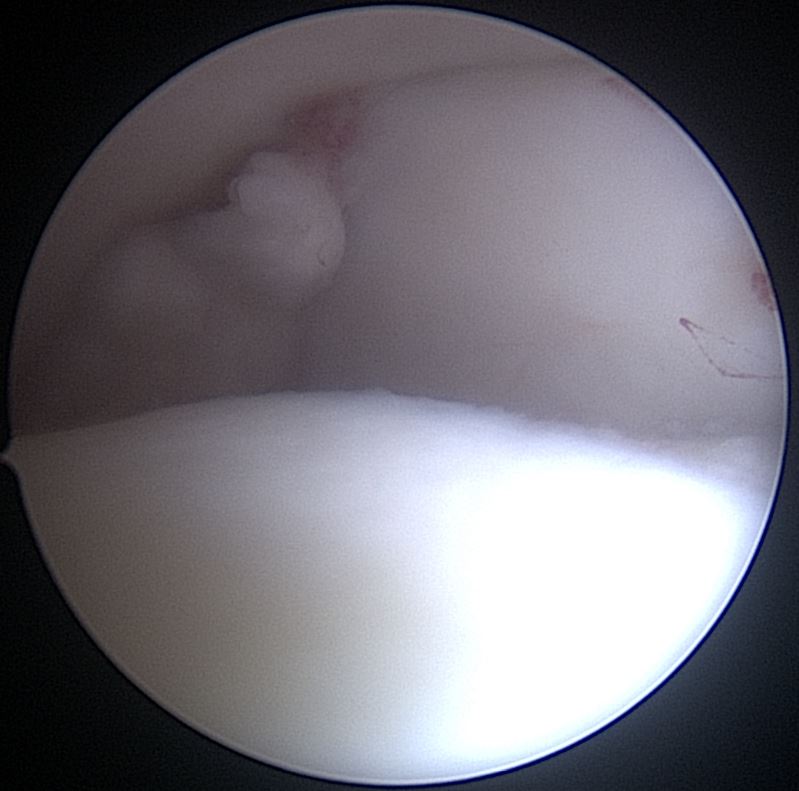

Home Schwerpunkte Krankheitsbilder Impingement Sprunggelenk Knochenfragment hintere Kammer OSg eingeklemmt ASKp Bild

Knochenfragment hintere Kammer OSg eingeklemmt ASKp Bild